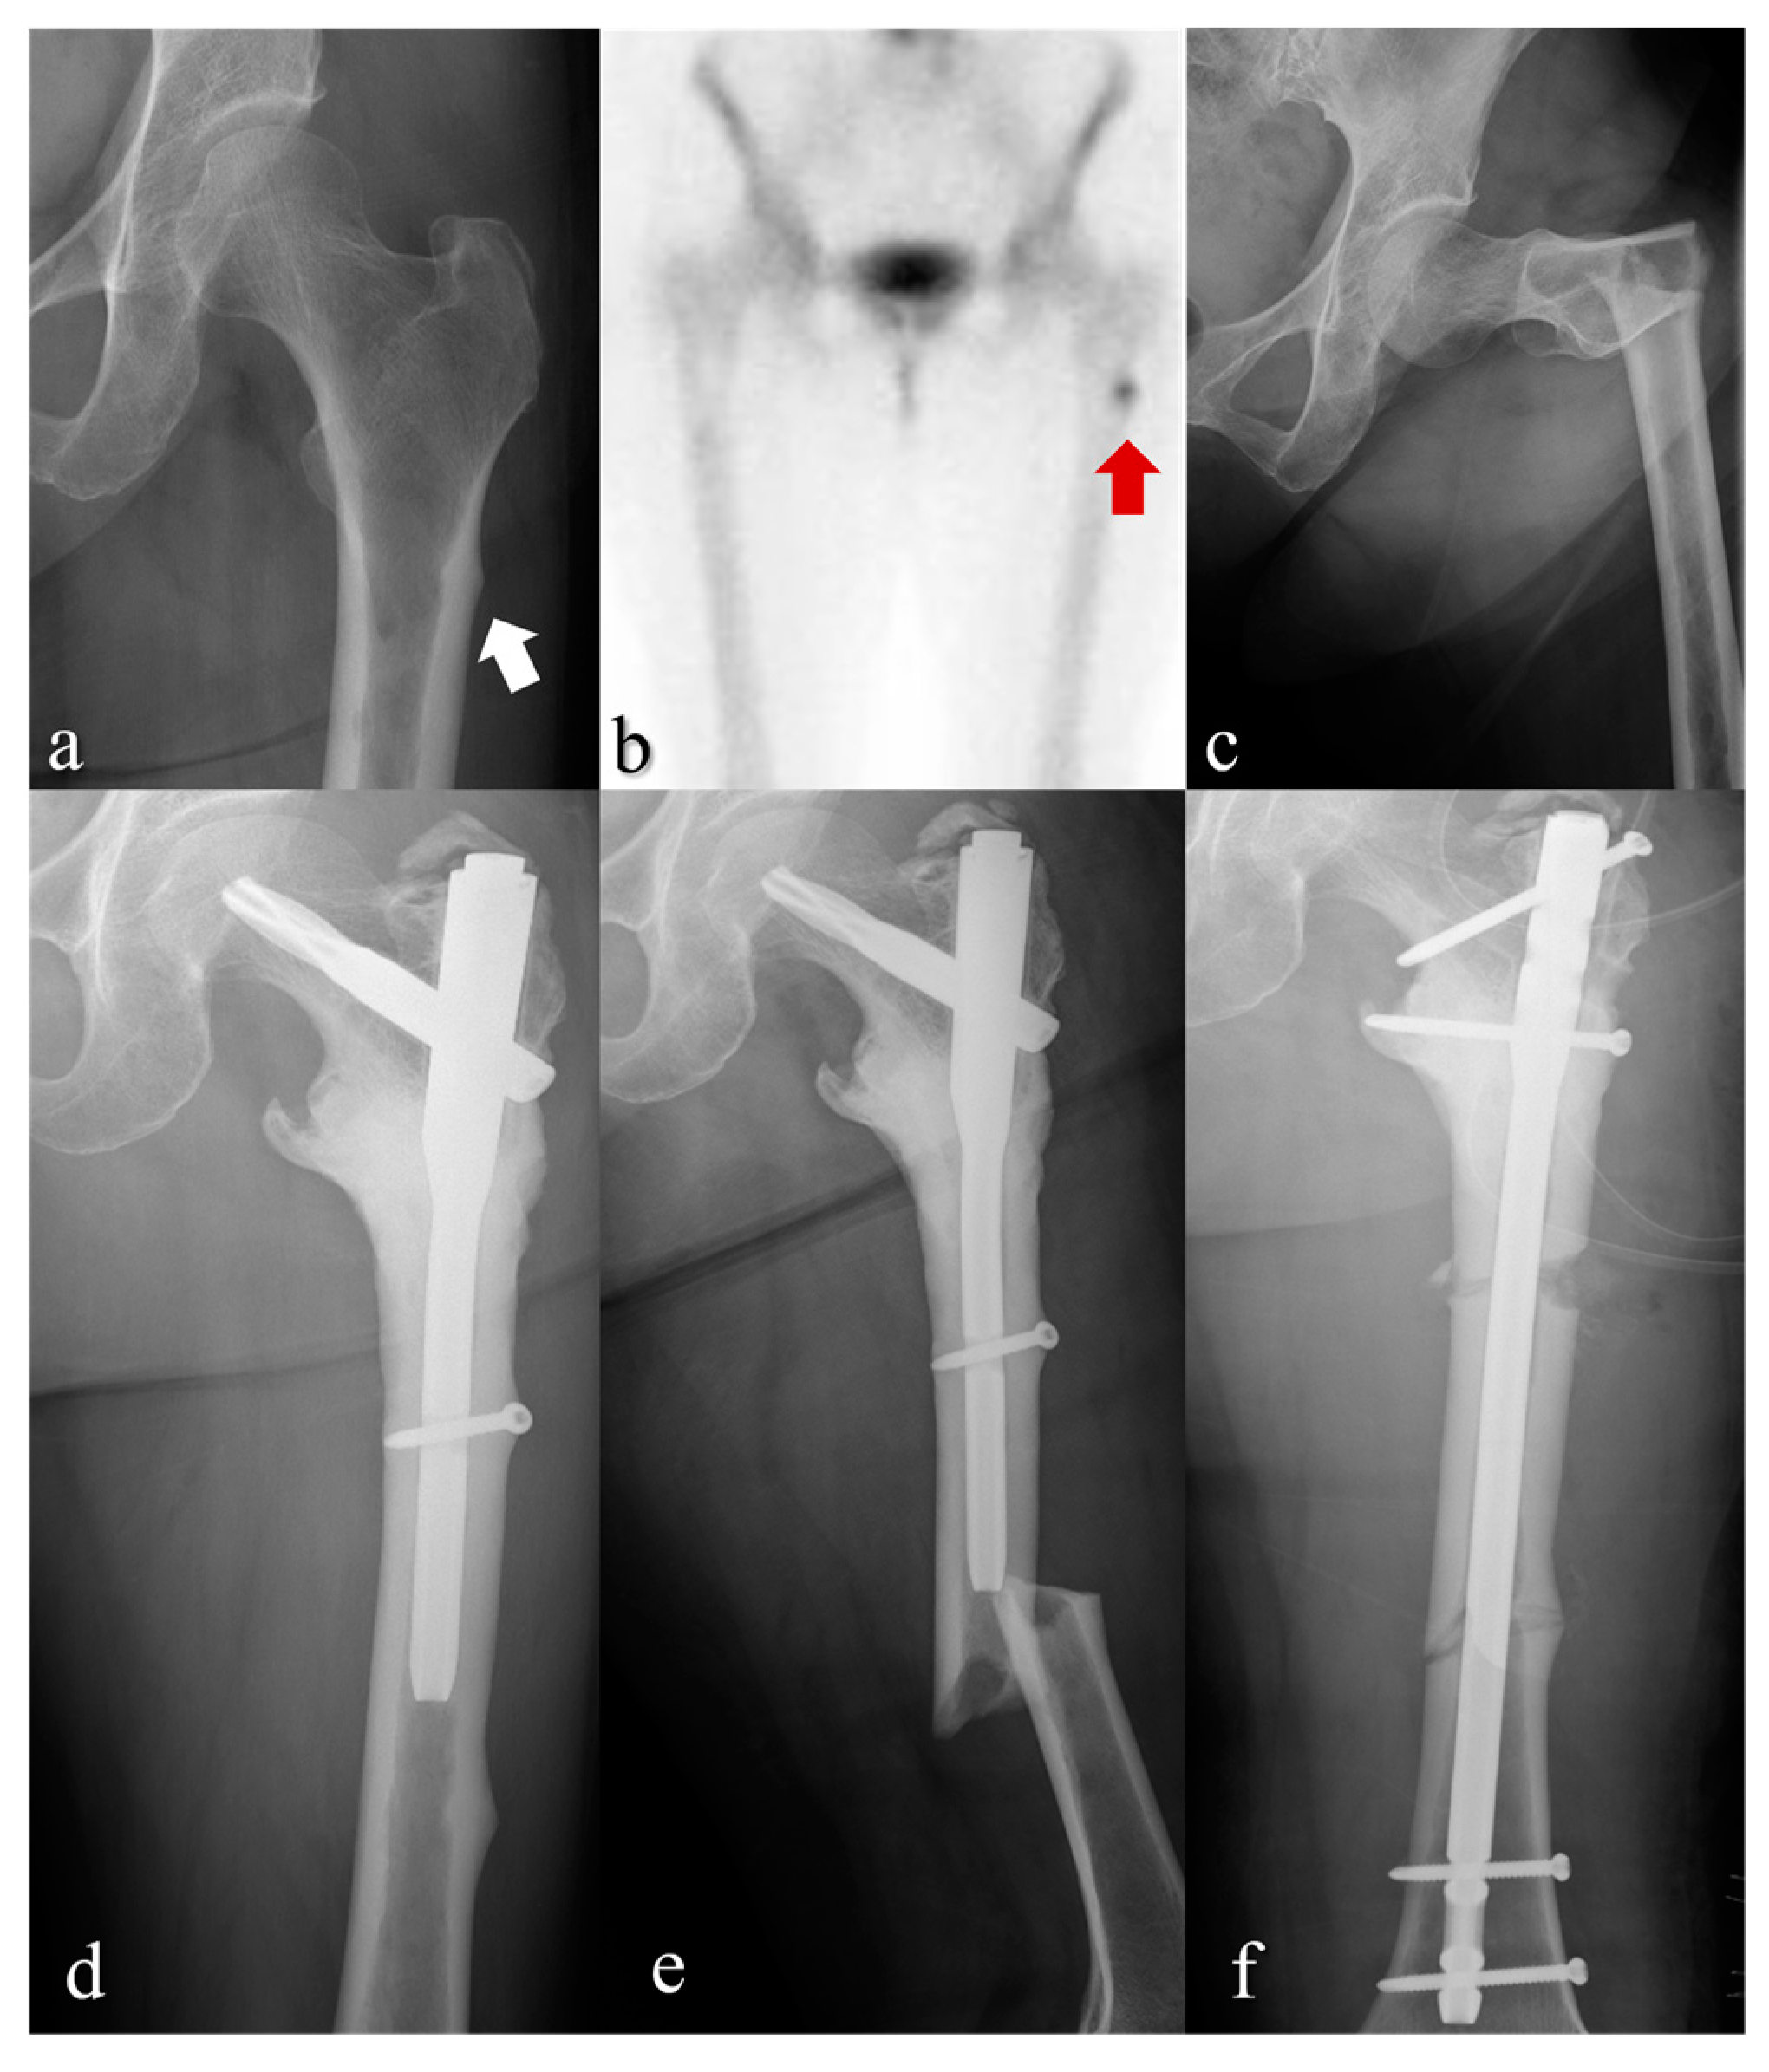

- Schilcher, J.; Michaëlsson, K.; Aspenberg, P. Bisphosphonate use and atypical fractures of the femoral shaft. N. Engl. J. Med. 2011, 364, 1728–1737. [Google Scholar] [CrossRef]

- Shane, E.; Burr, D.; Abrahamsen, B.; Adler, R.A.; Brown, T.D.; Cheung, A.M.; Cosman, F.; Curtis, J.R.; Dell, R.; Dempster, D.W. Atypical subtrochanteric and diaphyseal femoral fractures: Second report of a task force of the American Society for Bone and Mineral Research. J. Bone Miner. Res. 2014, 29, 1–23. [Google Scholar] [CrossRef] [PubMed]

- Chang, S.T.; Tenforde, A.S.; Grimsrud, C.D.; O’Ryan, F.S.; Gonzalez, J.R.; Baer, D.M.; Chandra, M.; Lo, J.C. Atypical femur fractures among breast cancer and multiple myeloma patients receiving intravenous bisphosphonate therapy. Bone 2012, 51, 524–527. [Google Scholar] [CrossRef]